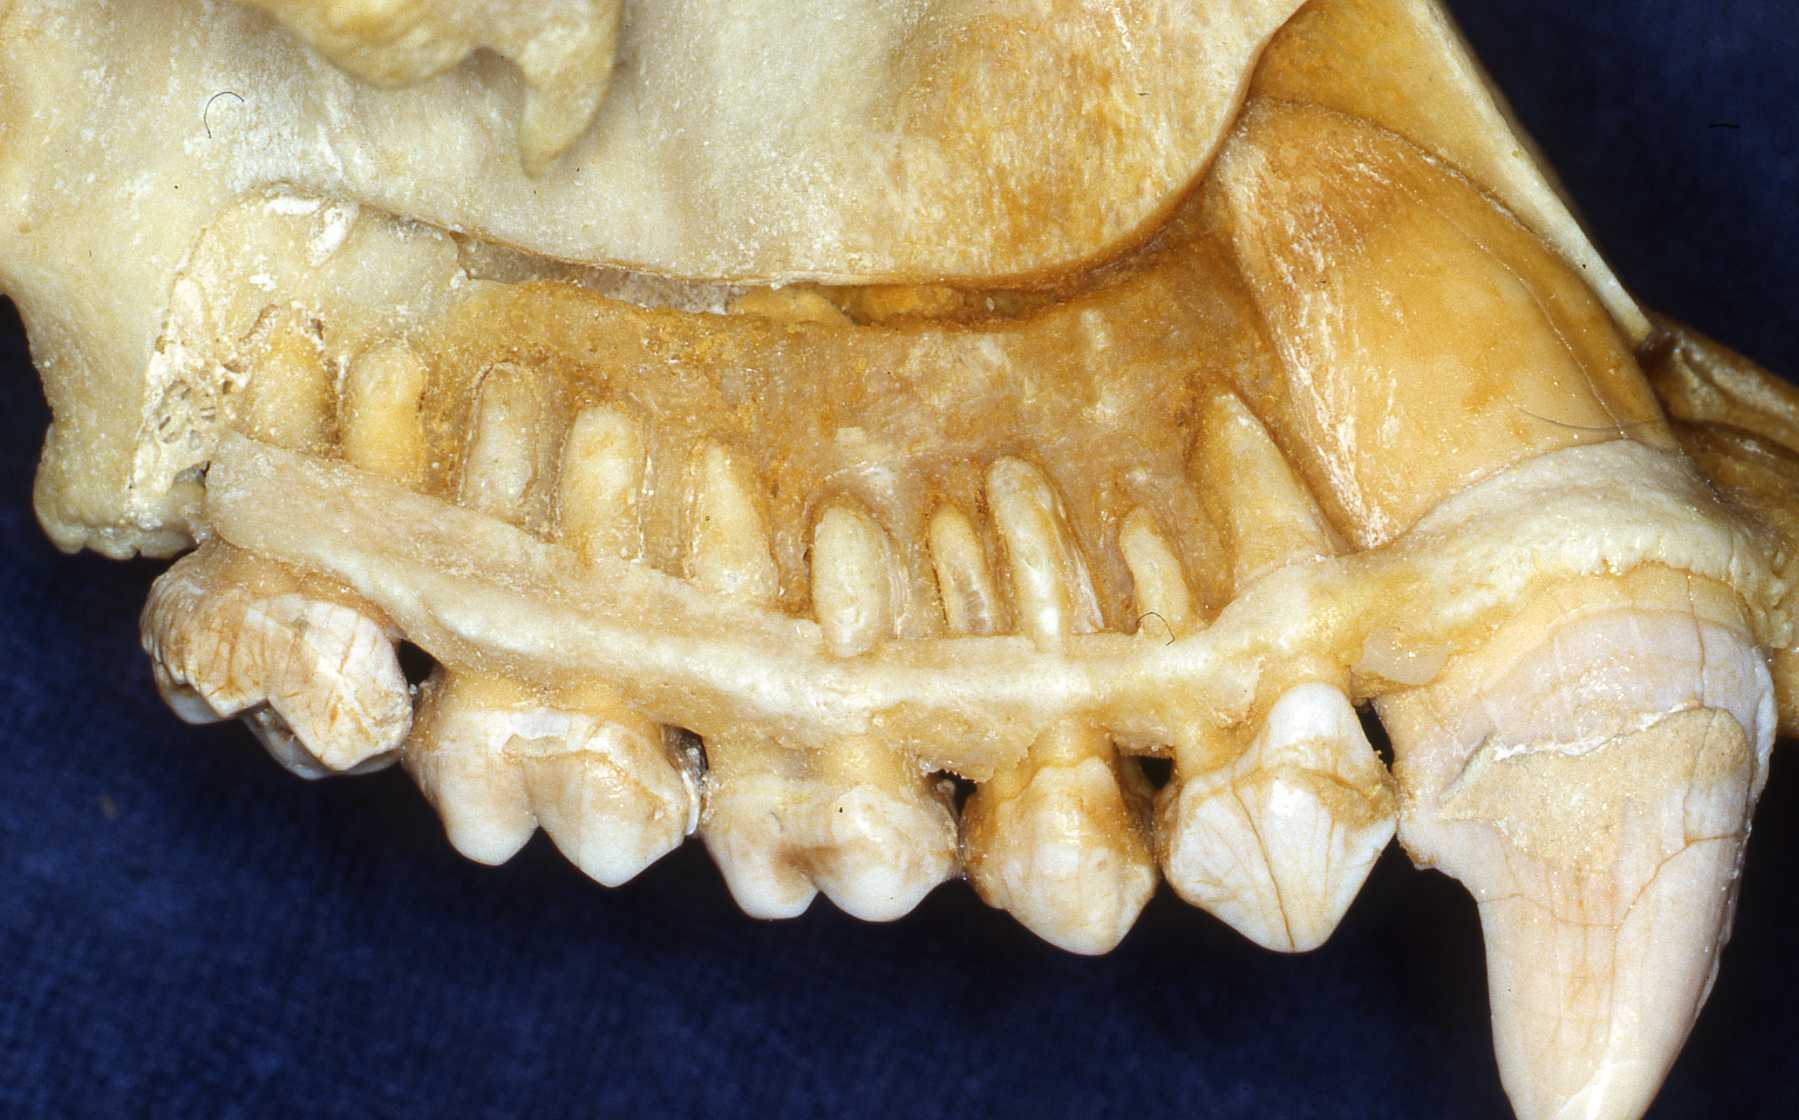

Use references such as those listed on this site. Radiographs of the particular species are very helpful. Skull and teeth collections are the optimum for preparation. I have encouraged accumulating a collection at our zoo and we have established an archive from animals that died at Milwaukee County Zoo. Over the years I established a relationship with the Milwaukee County Museum and the Zoological Museum at the University of Wisconsin, Madison. They receive the carcasses of our animals after pathologists evaluate them. Then the animals' skeletons are added to their or our collection.

The apes will have the same number of teeth as humans. That is 20 primary teeth and 32 permanent teeth. The same is true for the old world monkeys. Some new world monkeys have three premolars per quadrant. Other primate groups have various dental formulae. The primate teeth are anelodont with very few exceptions (aye-aye for example). There are also variations in numbers of roots. Therefore, again, preoperative radiographs should always be reviewed prior to extraction or endodontic procedures. The root apices usually have single orifices with a small percentage having auxiliary canal openings or perhaps two apical openings as often found in humans.

We have also encountered anatomic variations and anomalies in several species such as supernumerary teeth and impactions. Again, knowing the "normal" situation and always taking preoperative radiographs is necessary to recognize such situations. Such variations and anomalies do not necessarily warrant treatment unless they are causing or will very likely lead to pathosis.

Tommy Orangutann, young adult, impacted mandibular premolar case